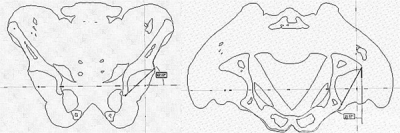

个性化脊柱导航模板的设计方法基本一致,在众多的方法中,这里我们介绍其中一种利用投影的手段来确定植钉最佳植钉通道。我们基于脊柱CT连续断层数据,通过序列预处理的过程,生成STL格式的三维模型,再通过UG imageware12.0软件确定椎弓根螺钉的最佳进钉通道。首先获得椎弓根的正投影,其内侧壁投影为椎弓根的进钉最小参考通道(图1)。连接两个正投影的中点即可以得到椎弓根螺钉的最佳进钉通道。利用Magics9.5软件测量工具还可以获得实际植钉所需要的椎弓根螺钉的参数,为实际植钉提供可靠的参照。

图1. 利用逆向工程软件确定椎弓根螺钉植入通道

(a) 椎弓根的正投影 (b) 椎弓根螺钉最佳位置的正投影

(c) 椎弓根螺钉通道 (d) 导航模板理想的导航管的方位。